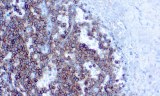

Primary antibodies for immunohistochemistry CE/IVD - Pediatric pathology

Perinatal/paediatric pathology is a medical subspecialty with particular expertise in diseases affecting the placenta, fetus, infant and child. Although many conditions that affect adults also affect children, pediatric pathology includes many conditions found only in patients younger than 18 years of age. One group of conditions involving the infant population is congenital anomalies. A malformation is a congenital anomaly due to an intrinsic defect in development. A disruption occurs when a normally developing organ is secondarily damaged by another process. A sequence is a collection of several anomalies, all of which are due to one malformation, disruption, or deformation. Finally, a syndrome is a group of related anomalies. An other group is the pediatric cancers or childhood cancers. Childhood cancers include many that also occur in adults. Leukemia is by far the most common, representing about 33% of childhood cancers, brain tumors represent about 25%, lymphomas represent about 8%, and certain bone cancers (osteosarcoma and Ewing sarcoma) represent about 4%.